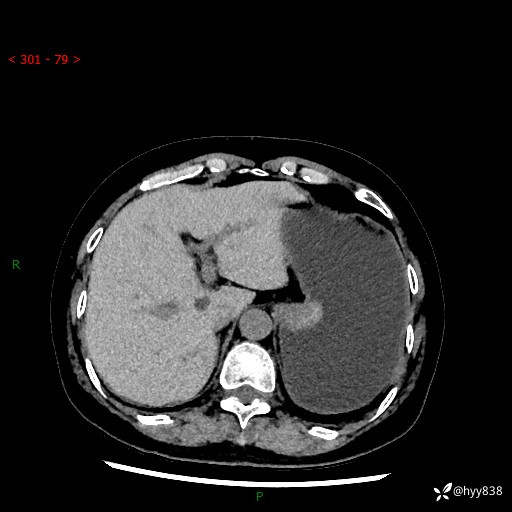

胃CT平扫+增强(动脉期+静脉期)

三期CT值:46hu 58hu 75hu